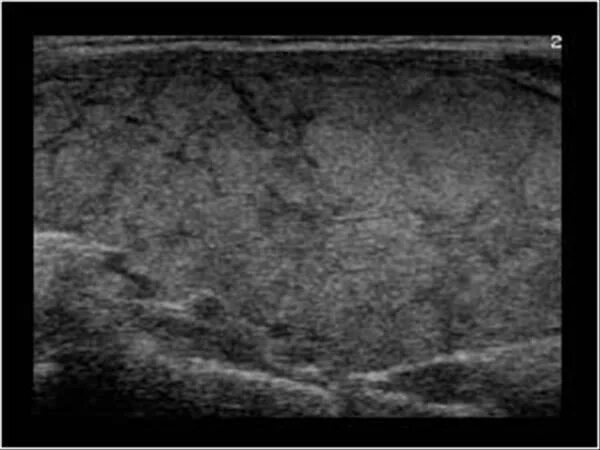

Диффузные изменения щитовидной железы на узи